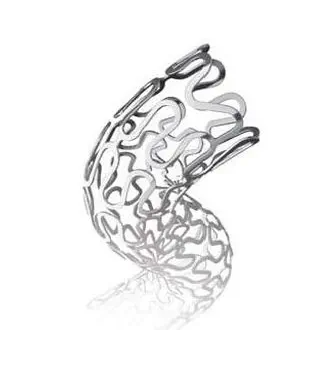

Gureater ™ CoCr Stent with Sirolimus Coating

GuReater™ is a Cobalt-Chrome drug-eluting stent coated with Sirolimus.

Its 75 μm CoCr struts provide excellent flexibility and crossability, ensuring optimal vessel conformity after implantation.

Available in a wide range of sizes, the Gureater drug-eluting stent features a cobalt-chrome (CoCr) platform with a bioabsorbable polymer (PLGA) that promotes early endothelialisation, helping to prevent inflammation.

Combined with Sirolimus, it offers excellent drug-release control over a total period of 90 days. Its design ensures high flexibility, optimal crossability, and low recoil.

The Co-Cr stent offers high radiopacity and biocompatibility, providing an excellent balance between radial strength and flexibility.

75 µm CoCr Strut

Provide super flexibility and crossability

Ensure the great compliance after implantation